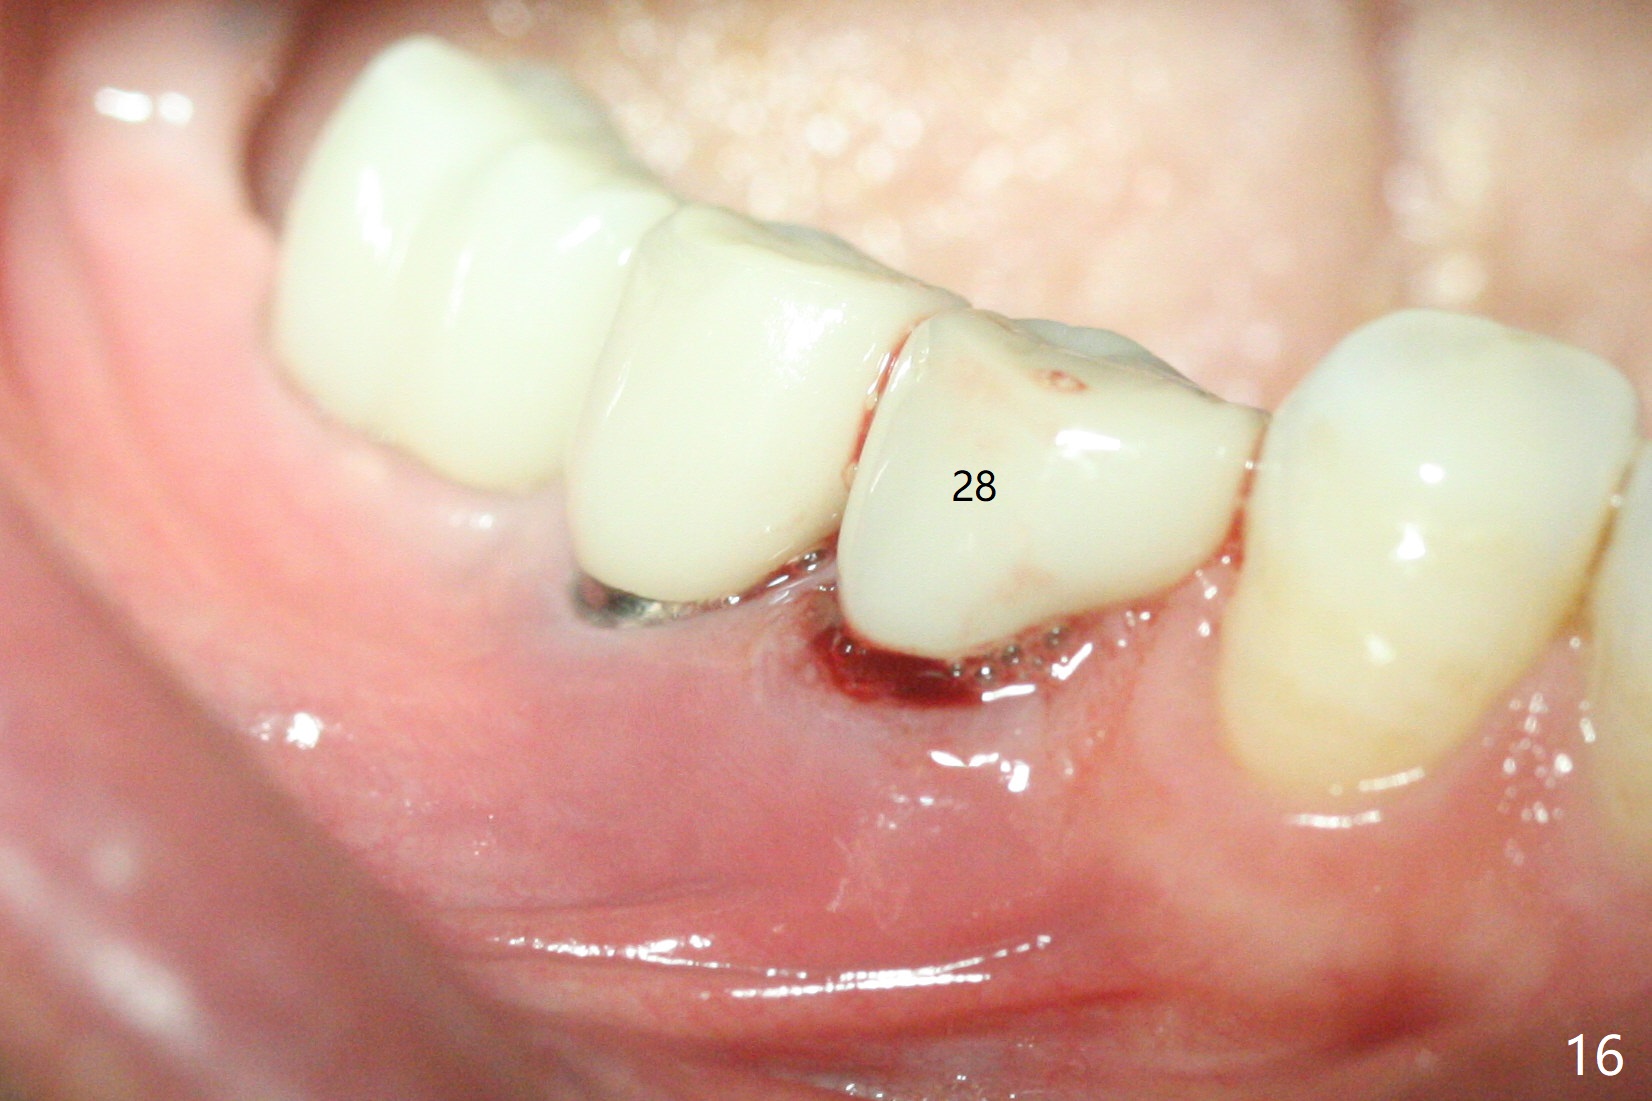

Two of 2.5 mm 1-Piece Implants M

The edentulous ridge at #30 is narrow (Fig.1). After ridge reduction, osteotomy is initiated with 1.2 mm drill for 10 mm; the mesial osteotomy is to be changed (Fig.2 red line). Using a 1.2 mm drill placed in the distal osteotomy (Fig.3 D), the mesial osteotomy changes in trajectory with subsequent placement of a 2.5x10(4) mm 1-piece implant. Since the mesial implant is high in occlusion, the cuff of the distal implant is changed to be 2 mm (Fig.4 (shorter black line)). Panoramic X-ray is taken to show no violation of the Inferior Alveolar Canal (Fig.5 red dashed line). These two 1-piece implants are slightly lingually placed (Fig.6). The crestal bone around the implants resorbs without thread exposure 5 months postop (Fig.7). Impression is taken for a splinted crown (Fig.8-12). There is no metal show around the 2.5 mm 1-piece implants 6 months postop (advantage) vs. that at #28 and 29 (Fig.13). Bitewing is taken post cementation to determine whether residual cement is present (Fig.14). There is periodic swelling and pain in the lower right quadrant 2 years post cementation (Fig.15). In fact periimplantitis appears to have developed at #28 (Fig.16) with loss of the buccal bone (Fig.17,18). The buccal bone loss is less at #29 (Fig.19) and #20 (Fig.23) and no at #30 mesial and distal implants (Fig.20,21). A much smaller implant will be placed lingually at #28 immediate (Fig.24,25).